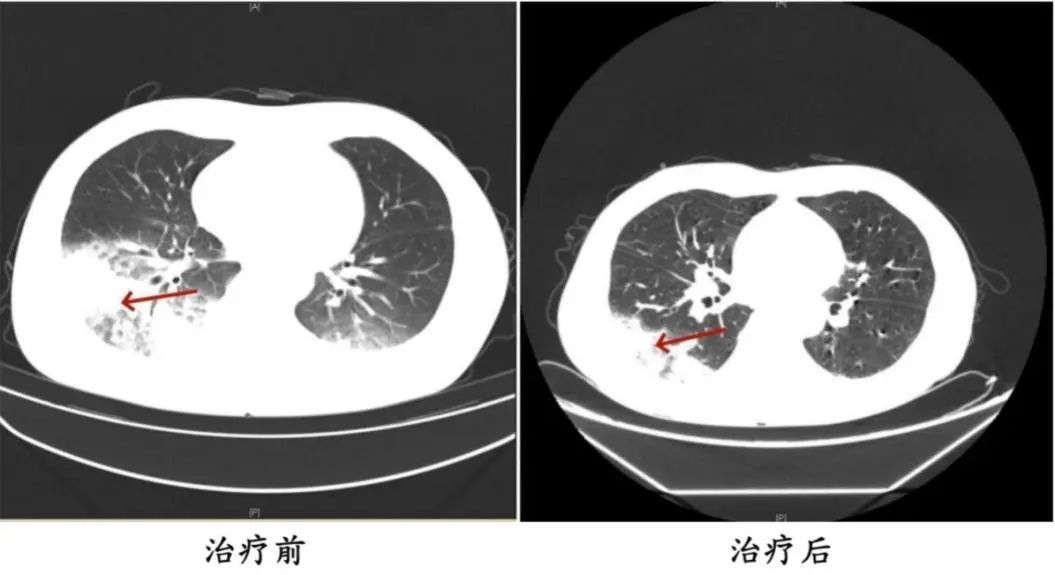

医生询问发现,周先生此前驾车出差,因为天气热,他启动了久未清洗的车载空调,每天在车上的时间超过十个小时,回来后就出现了如上症状。经过检查,最终确诊为军团菌肺炎。

△周先生治疗前后的肺部CT影像